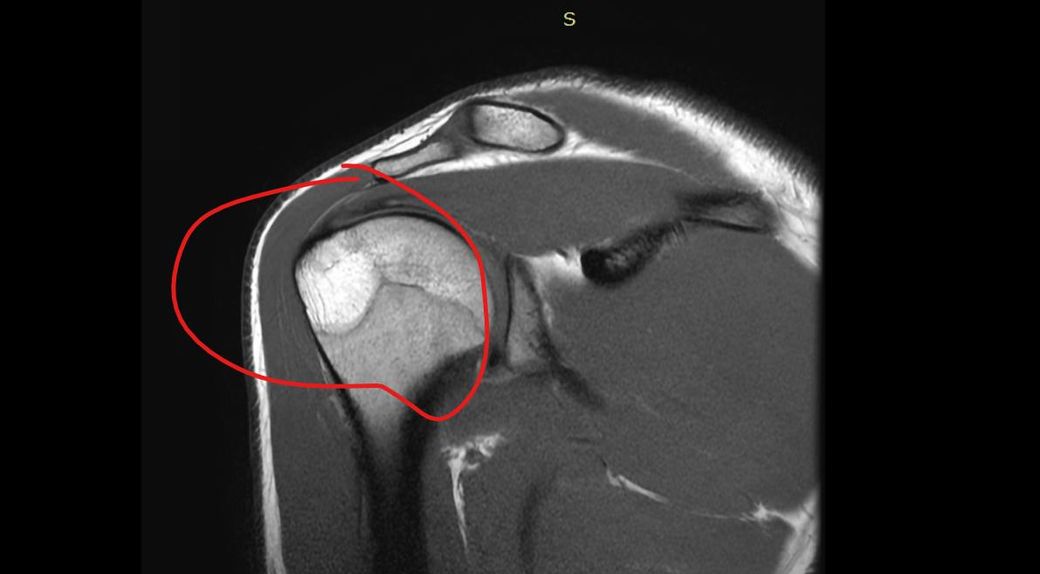

어깨 골수부종인가요 ? 뼈멍인가요 미세골절인가요 사고나고 뼈에 심하게 멍들었다고 했긴했습니다 전 잘모르겠어서 질문 해봅니다

• 2번 째 사진

사진만으로 단정은 어렵지만, 표시된 소견은 보통 “골수부종(=뼈멍)”에 가장 가깝습니다.

골수부종은 “강한 충격 후 뼈 안에 물이 찬 상태“로, 미세골절과 영상상 겹쳐 보일 수 있습니다.